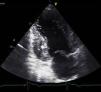

Mulher de 34 anos, com antecedentes de tabagismo, foi observada por palpitações rápidas com 12 anos de evolução. As queixas eram diárias, de curta duração e não se associavam a tonturas, síncope ou dor torácica. Não tinha antecedentes familiares de morte súbita, mas foi diagnosticado ao pai uma miocardiopatia dilatada idiopática. Como parte da avaliação realizou eletrocardiograma que revelou bradicardia sinusal, 36 b.p.m., critérios de hipertrofia ventricular esquerda, progressão anormal da onda R nas precordiais, ondas q não patológicas e alterações inespecíficas da repolarização ventricular em DII, DIII, aVF, V3-V6 e QTc longo. O ecocardiograma mostrou cavidades cardíacas não dilatadas, com boa função sistólica biventricular. O ventrículo esquerdo (VE) apresentava hipertrofia não obstrutiva dos segmentos basais do septo anterior, septo inferior e parede inferior (Figura 1), com uma espessura máxima de 21mm. A nível apical e, em particular, nos segmentos apicais da parede posterior e lateral observou-se uma hipertrabeculação (Figuras 2 e 3). A relação da camada não compactada com a compactada foi de 2,3, medida na incidência paraesternal eixo curto, no final da sístole. A injeção de contraste permitiu evidenciar a não compactação do miocárdio a nível apical (Figura 4). Para melhor caracterizar a morfologia cardíaca, realizou uma ressonância magnética (RM) que confirmou a presença da hipertrofia assimétrica do VE associada a uma não compactação do VE (Figura 5), com uma relação da camada não compactada com a compactada de 3,3, medida no fim da diástole. A RM adicionalmente revelou múltiplas áreas de realce tardio nos segmentos com hipertrofia. O Holter não mostrou disritmias com significado clínico e a prova de esforço revelou evolução tensional normal. A doente ficou assintomática após início de terapêutica com bisoprolol. O estudo ecocardiográfico dos familiares foi negativo quer para miocardiopatia hipertrófica (MCH) quer para a não compactação do ventrículo esquerdo (NCVE). O estudo genético identificou a mutação G1505A no exão 17 do gene MYBPC3 que leva à substituição de um aminoácido na posição 502da proteína (Arg502Gln).